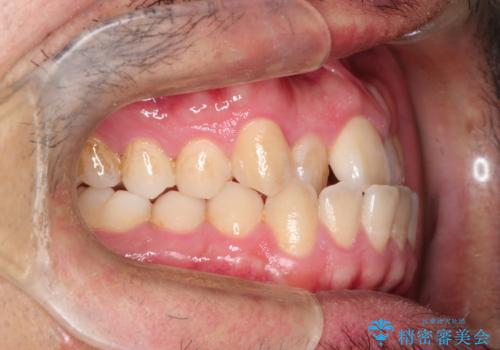

前歯が反対にかんでいる インビザラインとワイヤーを組み合わせた矯正治療

- 前歯が正常とは反対にかんでいるとのことで、来院されました。

患者様がマウスピースを希望されていましたが、上の前歯のがたつきを先にワイヤーで改善する方が早く治療が終了することが可能であるとお伝えし、上顎のみ半年間ワイヤーで治療を行いました。